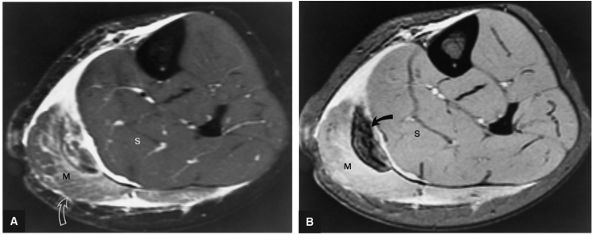

FIGURE 5.86 ● The accessory soleus muscle (A, sagittal image; B and C, axial images) originates from the anterior surface of the soleus or from the fibula and soleal line of the tibia. The variable insertion of the accessory soleus includes sites along the Achilles tendon, the superior surface of calcaneus, the muscle or fleshy insertion on the superior surface of the calcaneus, the muscular or fleshy insertion on the medial calcaneus, and the tendinous insertion on the medial calcaneus.